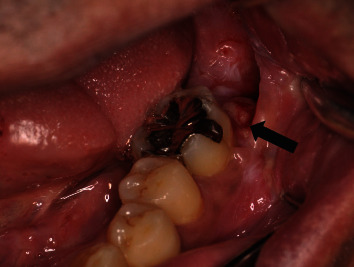

Figure 3.

Reddish granular tissue that easily bleeds is observed protruding from the mesial wall of the extraction socket of the second mandible (arrow).